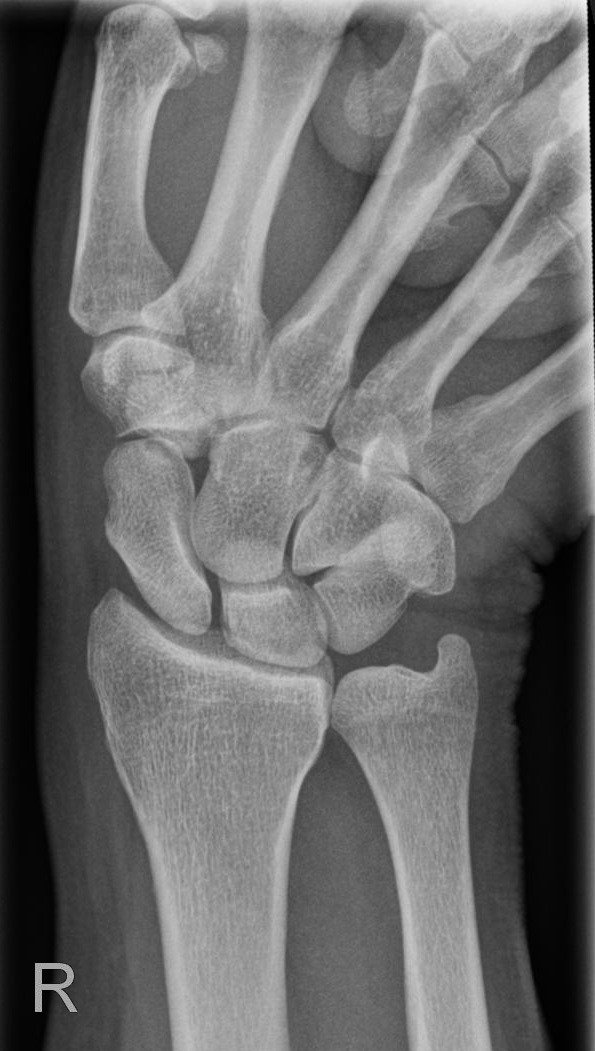

Handgelenk dorso-volar (1. Ebene)

Indikation

Fraktur

Darstellung der Handwurzel- und Unterarmknochen, bei Fragestellung von Epiphysenlösung, Grünholz- oder Os scaphoideumfraktur. Zur Beurteilung der Knochenkerne bei Kindern werden Vergleichsaufnahmen notwendig, bei Verdacht auf Subluxation des Os Lunatums, Zusatzaufnahme in Flextion und Reflextion der Hand notwendig (siehe Stressaufnahme).

Qualitätskriterien

Vollständige Abbildung der Metacarpalia, Handwurzelknochen und distaler Unterarm.